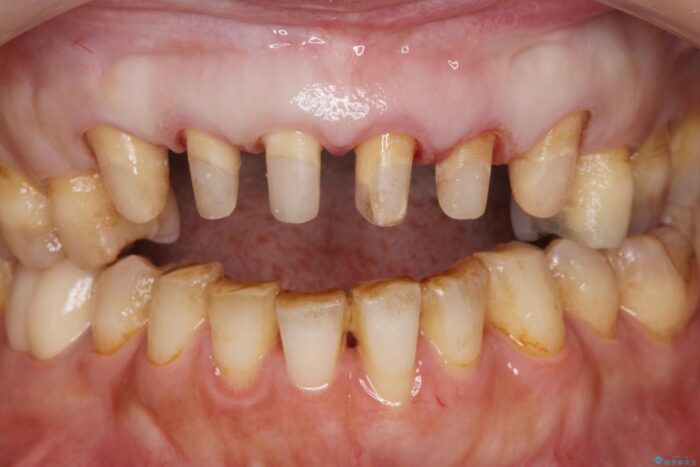

以前に他院で行ったセラミック治療後に、慢性的に歯ぐきからの出血や疼き、違和感がありご相談にいらっしゃった患者様です。

治療計画

装着されていたセラミックを除去したところ、歯ぐきの奥深くまで歯牙は削られ、歯ぐきの炎症・出血が著しくみられる状態でした。